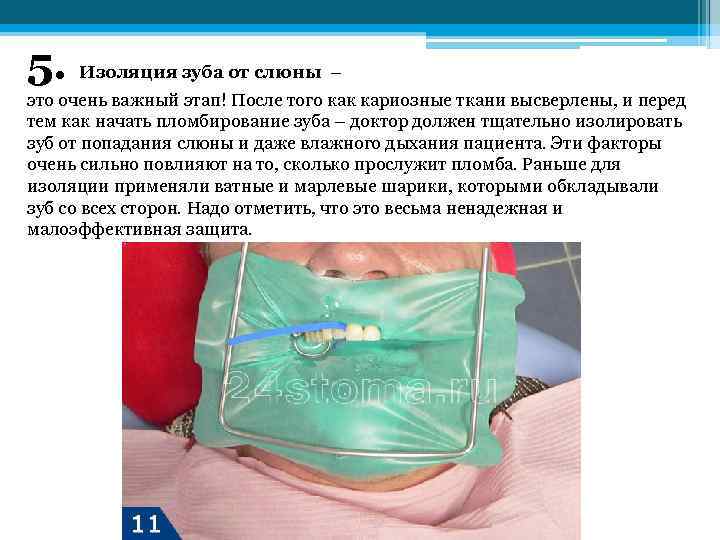

5. Изоляция зуба от слюны – это очень важный этап! После того как кариозные ткани высверлены, и перед тем как начать пломбирование зуба – доктор должен тщательно изолировать зуб от попадания слюны и даже влажного дыхания пациента. Эти факторы очень сильно повлияют на то, сколько прослужит пломба. Раньше для изоляции применяли ватные и марлевые шарики, которыми обкладывали зуб со всех сторон. Надо отметить, что это весьма ненадежная и малоэффективная защита.

5. Изоляция зуба от слюны – это очень важный этап! После того как кариозные ткани высверлены, и перед тем как начать пломбирование зуба – доктор должен тщательно изолировать зуб от попадания слюны и даже влажного дыхания пациента. Эти факторы очень сильно повлияют на то, сколько прослужит пломба. Раньше для изоляции применяли ватные и марлевые шарики, которыми обкладывали зуб со всех сторон. Надо отметить, что это весьма ненадежная и малоэффективная защита.